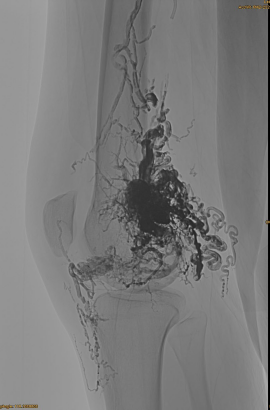

Osnovne informacije o pacijentu: žensko, 36 godina; AVM zdjelica, hip, koljeno, lijevo OSG, višestruke prije - embolizacije.

Korišteni proizvodi: 3pcs lava-34,14pcs lava-18.

Početna DSA:

Konačni rezultat:

Kasna faza, potrebna još jedna embo, ali puno bolje: